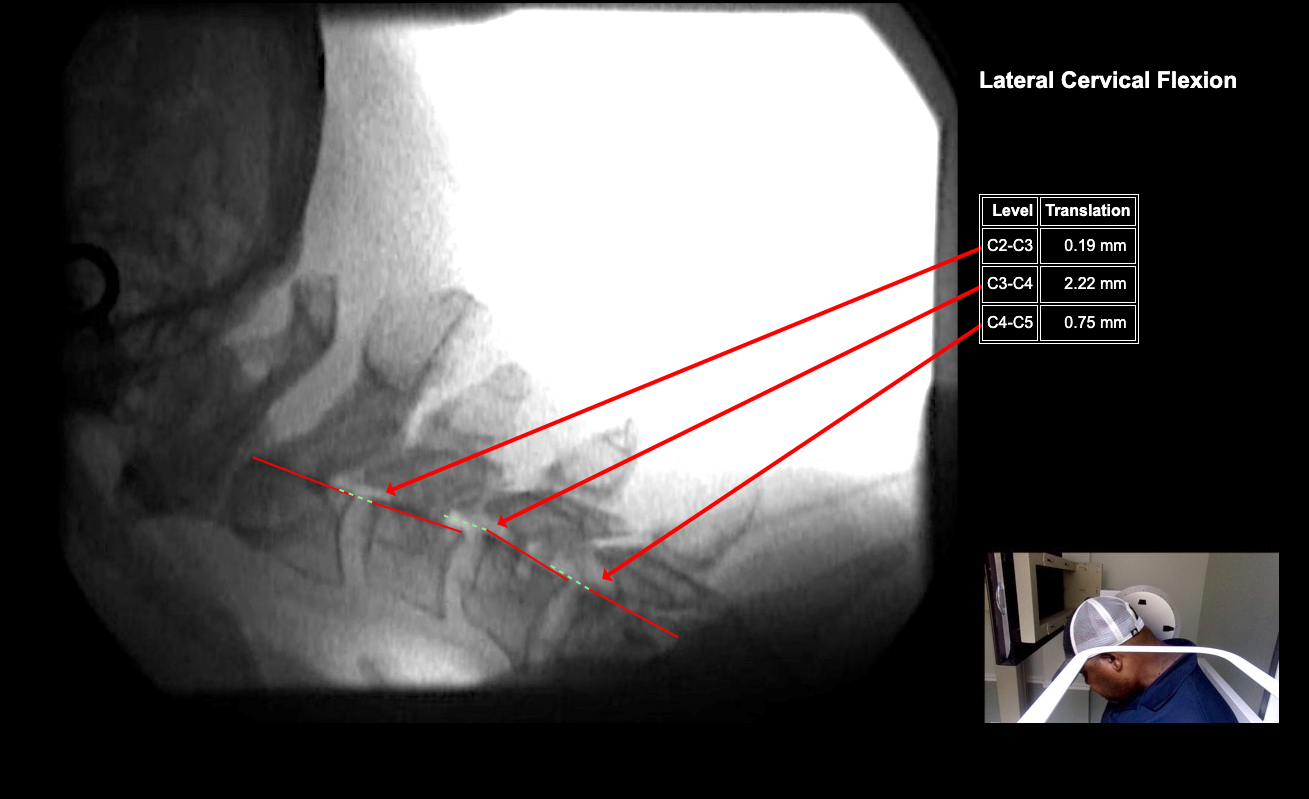

Image Name Image Type Image